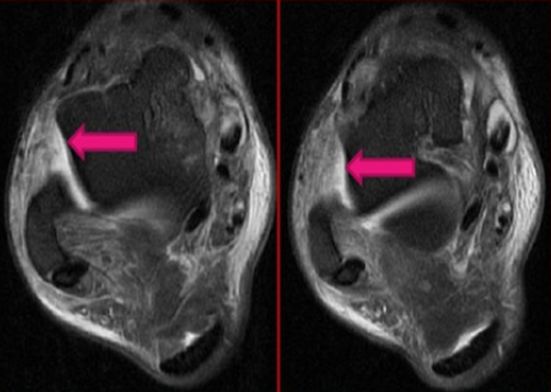

距腓前韧带撕裂

跟腓韧带撕裂